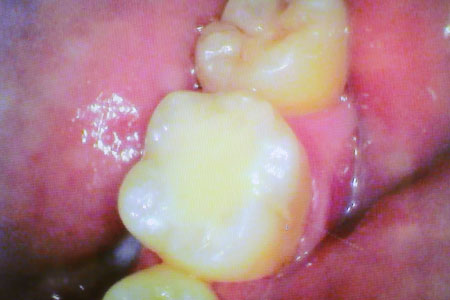

虫歯治療例 少し虫歯をとると大きな虫歯を発見

虫歯治療例 大きな虫歯